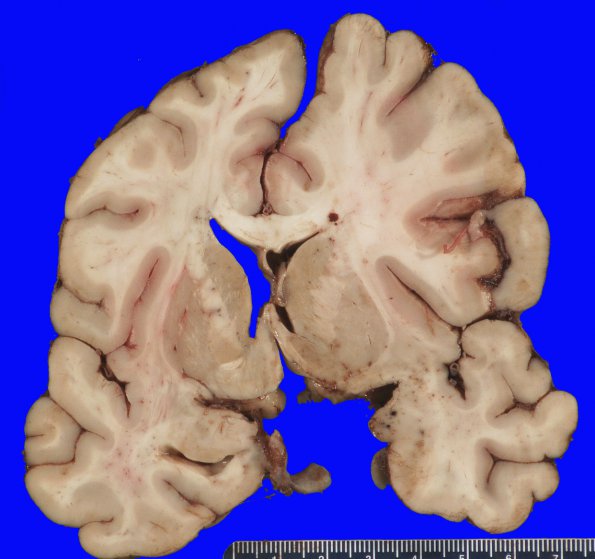

11B3,4 The right side does not appear flattened, probably because the bleed is acute. However there are hemorrhages in the right temporal lobe and collapse of the right lateral ventricle and cingulate gyrus